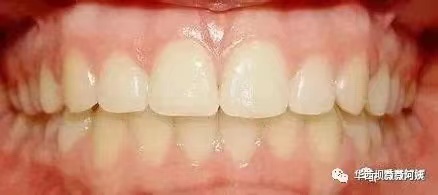

答:乳牙和恒牙本来就有很大区别。孩子新生的恒牙,尤其是门牙,相对来说会显得特别大。

孩子新长的恒牙体积更大,尤其是新长出来的门牙,与孩子的娃娃脸以及旁边的乳门牙不匹配,更容易让妈妈们感觉孩子长大板牙变丑了。

这是因为作为颜值担当,恒前牙匹配的是成年后的脸型。在整个替牙列期,孩子的颅面部都会持续生长发育,尤其是在青春期10-14岁,孩子的生长高峰来临,面部会发生翻天覆地的改变。俗话说得好,女大十八变,越变越好看。所谓的五官长开了,就是面部整体的发育变迁。

等孩子长大了,和发育完全的面部组织整体搭配,牙齿看起来就会更加和谐。所以不用担心,随着孩子其他牙齿的替换,以及颌面部组织的继续生长发育,这种不协调的状态慢慢就不存在了。